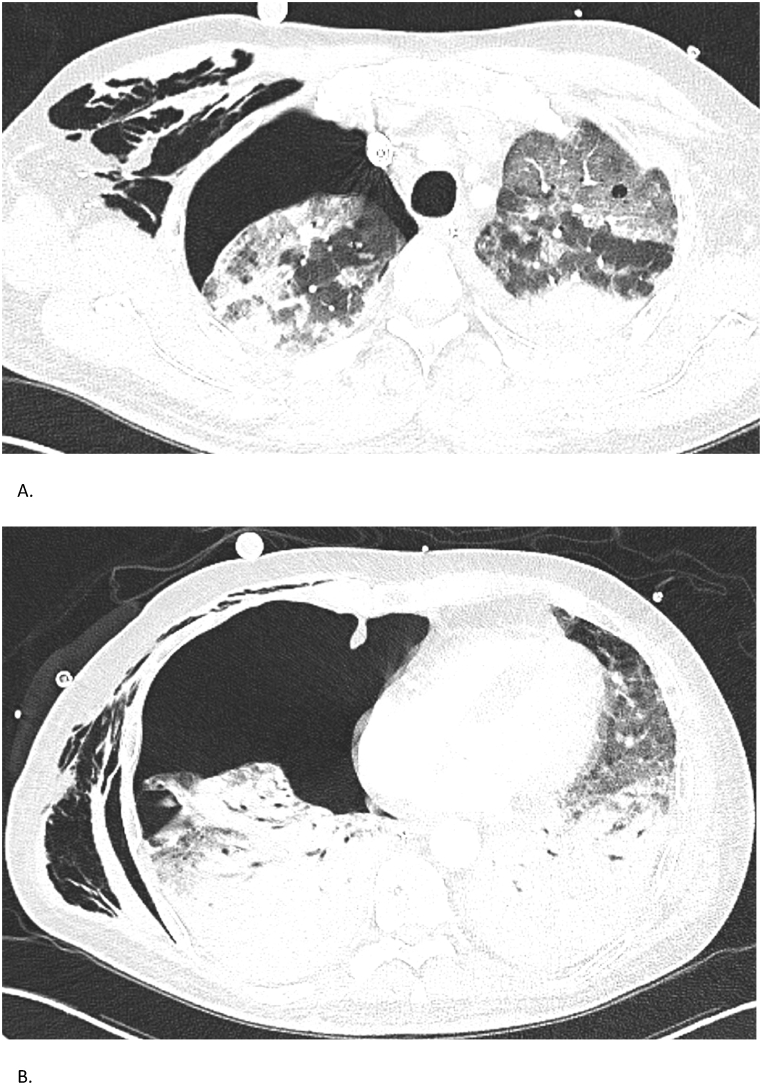

Fig. 2.

Case 2 – Chest CT findings

Chest CTs of a 51-year-old man with anti-MDA5-associated RP-ILD. (A, B) CT on November 10, 2022, reveals diffuse fibrotic changes with honeycombing and right-sided pneumothorax. Despite chest drainage, the lung shows incomplete re-expansion, consistent with trapped lung.

High-resolution chest CT revealed fibrotic interstitial lung disease with honeycombing and bronchiectasis, mainly affecting the lower lobes and right middle lobe. Shortly after ICU admission, the patient developed a right-sided pneumothorax, which was managed with chest tube drainage; however, the lung failed to re-expand, likely due to underlying fibrosis and alveolar damage (Fig. 2). Serologic testing showed markedly elevated anti-MDA5 IgG levels (72 %), which gradually declined to 8 % after initiation of immunosuppressive treatment.